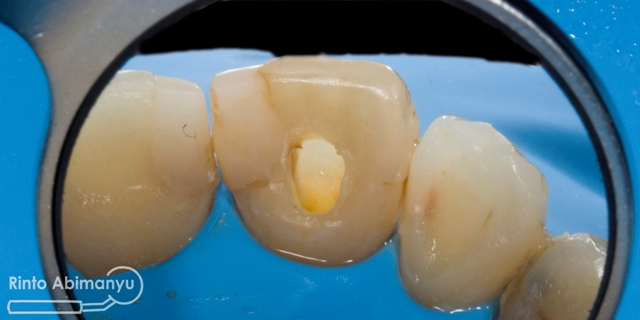

Gigi diisolasi kembali dengan rubber dam, kemudian gigi dilakukan preparasi saluran akar.. Saya menggunakan K-File sampai no.45, dan diirigasi menggunakan NaOCl 5,25% serta diaktivasi menggunakan menggunakan ultrasonic skeler dengan tip Irrisafe (Satelec).

Gigi 11 setelah preparasi saluran akar

Pengisian dilakukan menggunakan tehnik warm vertival condensation memakai Element Obturation Unit (SybronEndo), setelah itu untuk seal nya memakai SDR (Dentsply)..